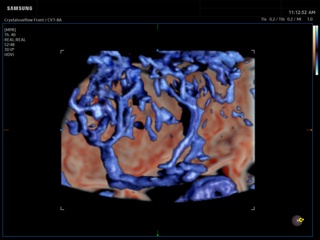

In the section "Оbsterics" of atlas the results of ultrasonic examinations of pregnant women with different durations of gestation are represented. Here you can see images of internally organs, cerebrum, cordis and the sex of the fetus, the sonograms of multiple pregnancy, the blood flow in placenta and umbilical cord, defects of fetal`s development, etc.